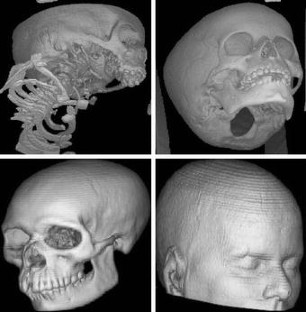

Fig 4.